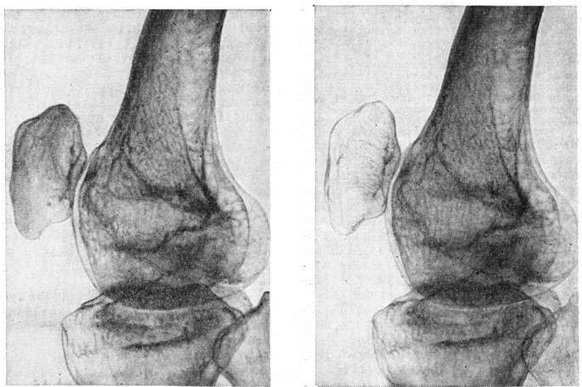

Прижизненное распознавание, определение характера и степени распространения Зудека атрофия возможно только с помощью рентгенографии. Учитывая разрежённость костной структуры, снимки производят «мягкие». Глубокие нейротрофические изменения тканей при Зудека атрофия на рентгенограмме проявляются в довольно быстром (спустя 7—10 дней от начала заболевания) возникновении остеопоротической перестройки костной структуры, имеющей вначале мелкоочаговый характер (рисунок). Густо сидящие, мелкие, округлой формы очажки разрежения придают костной ткани пятнистый вид. В дальнейшем в связи с быстрым нарастанием процессов рассасывания преимущественно второстепенных и поперечных костных балок и истончения кортикального слоя остеопороз приобретает диффузный характер, на фоне которого отчётливо видны системы костных балок, расположенных по силовым линиям и несущих основную функциональную нагрузку.